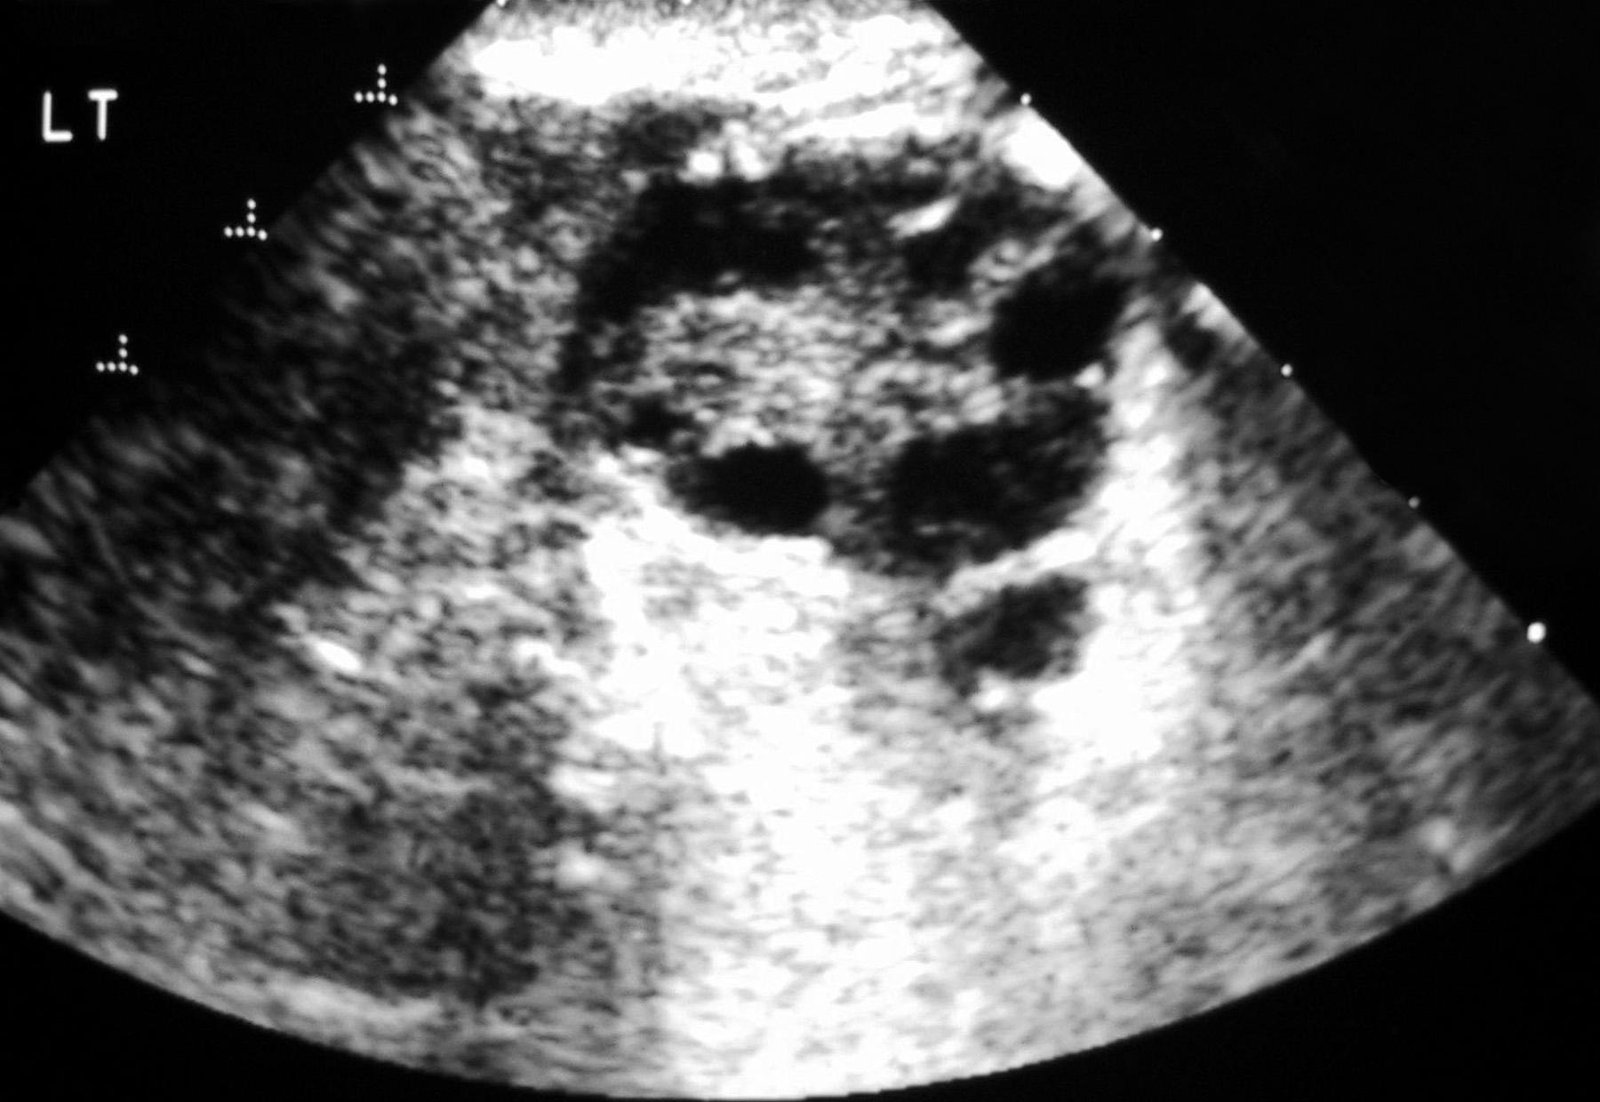

- Ультразвукове обстеження: щоб побачити наявність кіст на яєчниках.